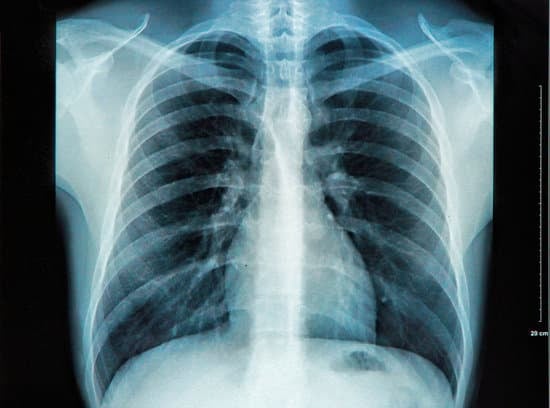

흉부 X선 촬영(Chest X-ray)은 가슴 부위를 X선으로 촬영하여 폐, 심장, 기도 등의 상태를 확인하는 의료 영상 검사입니다.

간단하고 빠르게 진행되는 검사로, 폐 질환, 심장 질환, 갈비뼈 이상 등을 진단하는 데 유용합니다.

폐와 기관지, 심장, 갈비뼈의 모양과 크기가 정상일 때는 특별한 소견이 없습니다.

폐렴, 폐결핵 등의 폐 질환이 있을 경우 폐에 흰색 음영이 나타납니다.

기흉의 경우, 폐가 수축되거나 폐 외부에 공기가 차는 소견이 보입니다.

심부전이나 심장비대의 경우, 심장의 크기가 비정상적으로 커져 있거나 흉막삼출이 보일 수 있습니다.

폐암의 경우, 폐에 혹이나 결절이 나타날 수 있습니다. 그러나 초기 폐암은 X선에서 확인되지 않을 수 있어 CT 스캔 등 추가 검사가 필요할 수 있습니다.